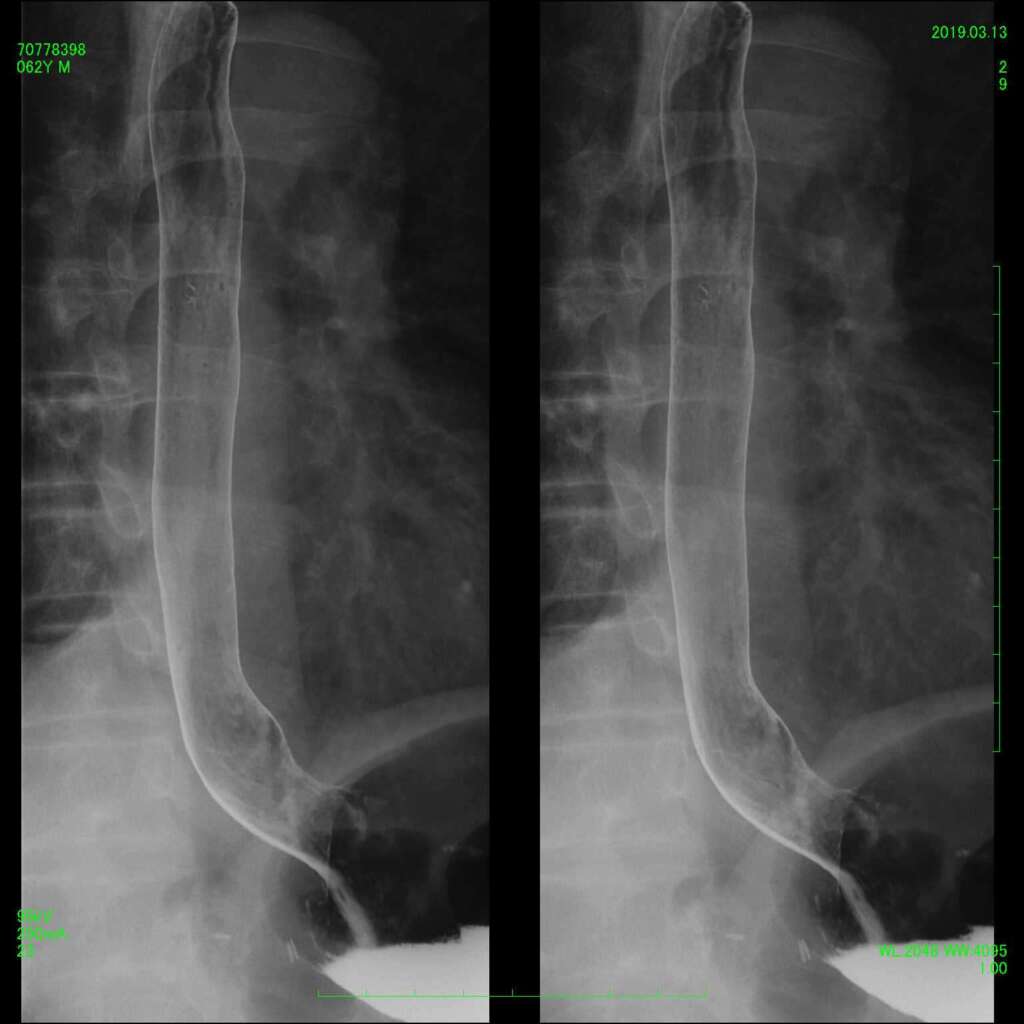

●脊髄腔造影(ミエログラフィー)/ 神経根ブロック

腰背部から針を刺し、脊髄腔にヨード造影剤を注入し、脊髄腔の形状や交通を観察する検査です。

脊柱管狭窄症や椎間板ヘルニアの診断に役立ちます。ミエログラフィーに引き続いて、痛みの原因部位に痛み止めを注射する神経根ブロックを続けて行う場合もあります。

腰部脊髄造影

脊髄腔は腰椎の後ろ側に位置し、頭から腰まで「丸い管」のように繋がっています。椎間板ヘルニア等があると脊髄腔が圧迫され、丸い形が窪んだ状態で描出されます(左図の赤矢印)。